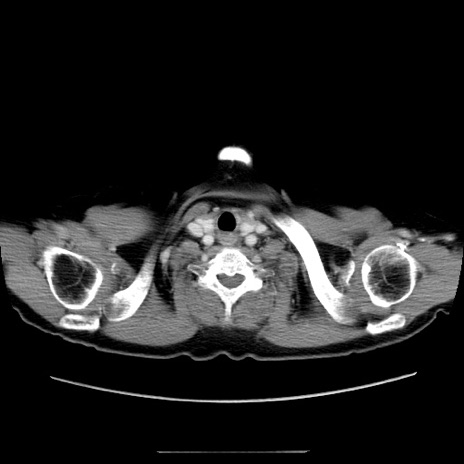

症例5(横断像)

【症例】70歳代女性

【主訴】お腹が張る

【現病歴】1週間くらい前から腹部膨満の自覚あり。昨日夜から増悪したため、本日救急外来受診。

【身体所見】意識清明、BT 36.5℃、BP 165/106mmHg、HR 80bpm、SpO2 98%、腹部:膨満、軟、自発痛・圧痛なし、触診にて不快感あり、腸蠕動音:減弱

【データ】WBC 12600、CRP 1.04